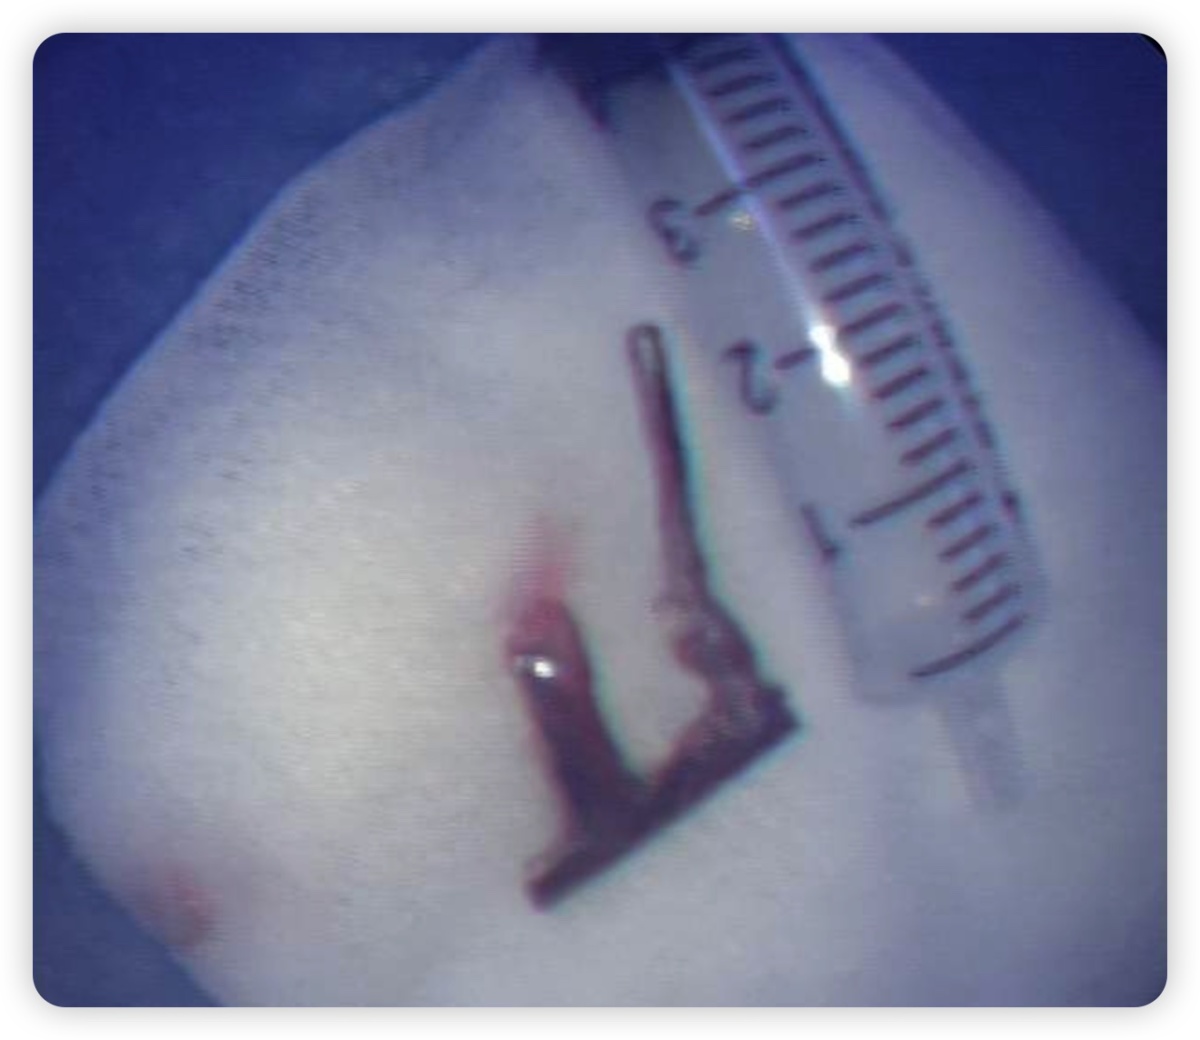

为避免气管镜操作时刺激患者剧烈咳嗽,内镜诊疗部刘薇医师及武秋菊主管护师在术前为患者进行局部麻醉,术中发现一“π”形异物卡顿于气管隆突及右主管口处,异物质地硬,似金属物,表面光滑,若贸然硬取可能会划伤患者支气管粘膜,在不断地调整角度后开始钳夹异物,气管镜缓慢移动并经过声门,最后将异物顺利取出。

王振静介绍说,气道异物是常见的临床急症之一,在我们内镜诊疗部的工作期间,遇到过许多气道异物的病例,比如鱼刺、辣椒、骨头等食物误吸。一般来说误吸异物后快速诊断、及早取出,对气道或肺实质的损害通常才会很小。异物滞留时间越长,越有可能出现各种并发症,轻则出现咳嗽、咳痰等肺部感染的症状,严重者甚至可能出现咯血、窒息等危及生命的情况。所以,大家在日常生活若不慎出现误吸或临床中发现气道异物,请尽快查胸部CT,评估病情后行支气管镜诊疗术,这样才可以有效地避免后续的损害。